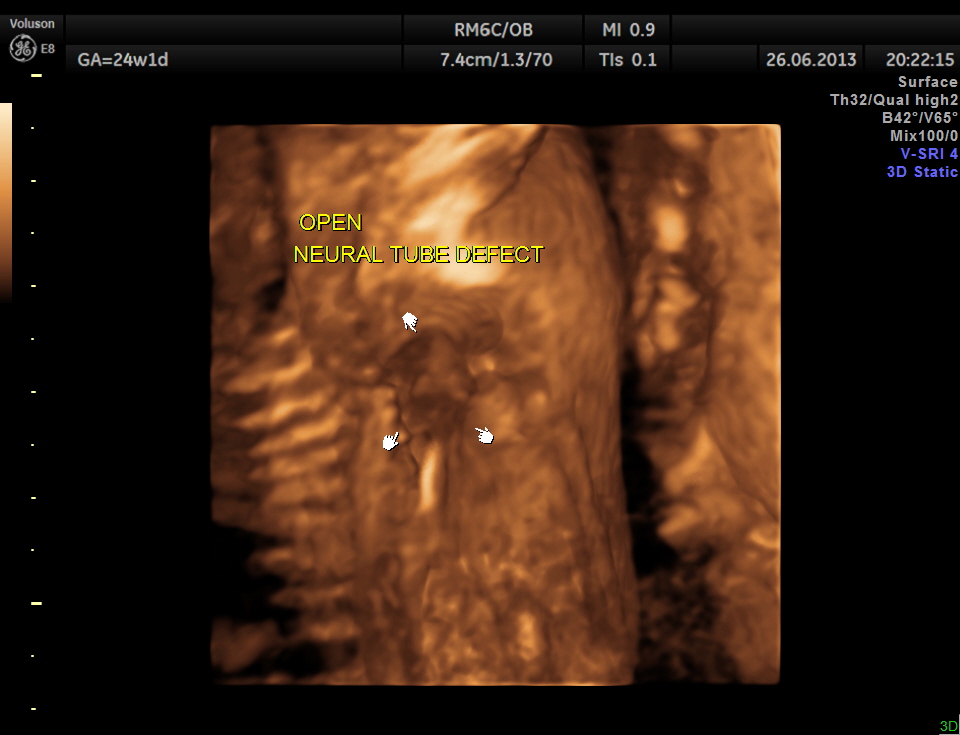

the following images are reconstructed images.

the following image shows the open neural tube defect at the same level as the heart.